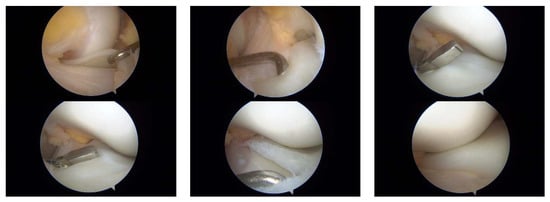

3.1. Case 1—P.E.

3.2. Case 2—S.C.S.

3.3. Case 3—G.L.

| P.E. | 12 | Bilateral (symptomatic right) | Chronic pain, effusion, normal ROM | None | 3 surgeries: partial meniscectomy (12 years), suture for horizontal tear (13 years), suture for radial tear (14 years) | 1 year after third surgery: symptom-free, resumed school sports |

| S.C.S. | 13 | Left | Pain, occasional locking, normal ROM | Dancing | 1 surgery: partial meniscectomy and suture for horizontal tear (13) | 6 months: symptom-free, full ROM, resumed dancing |

| G.L. | 14 | Bilateral (symptomatic right) | Pain, medial tenderness, normal ROM | Basketball | 1 surgery: partial meniscectomy and suture for horizontal tear (14) | 6 months: symptom-free, full ROM |